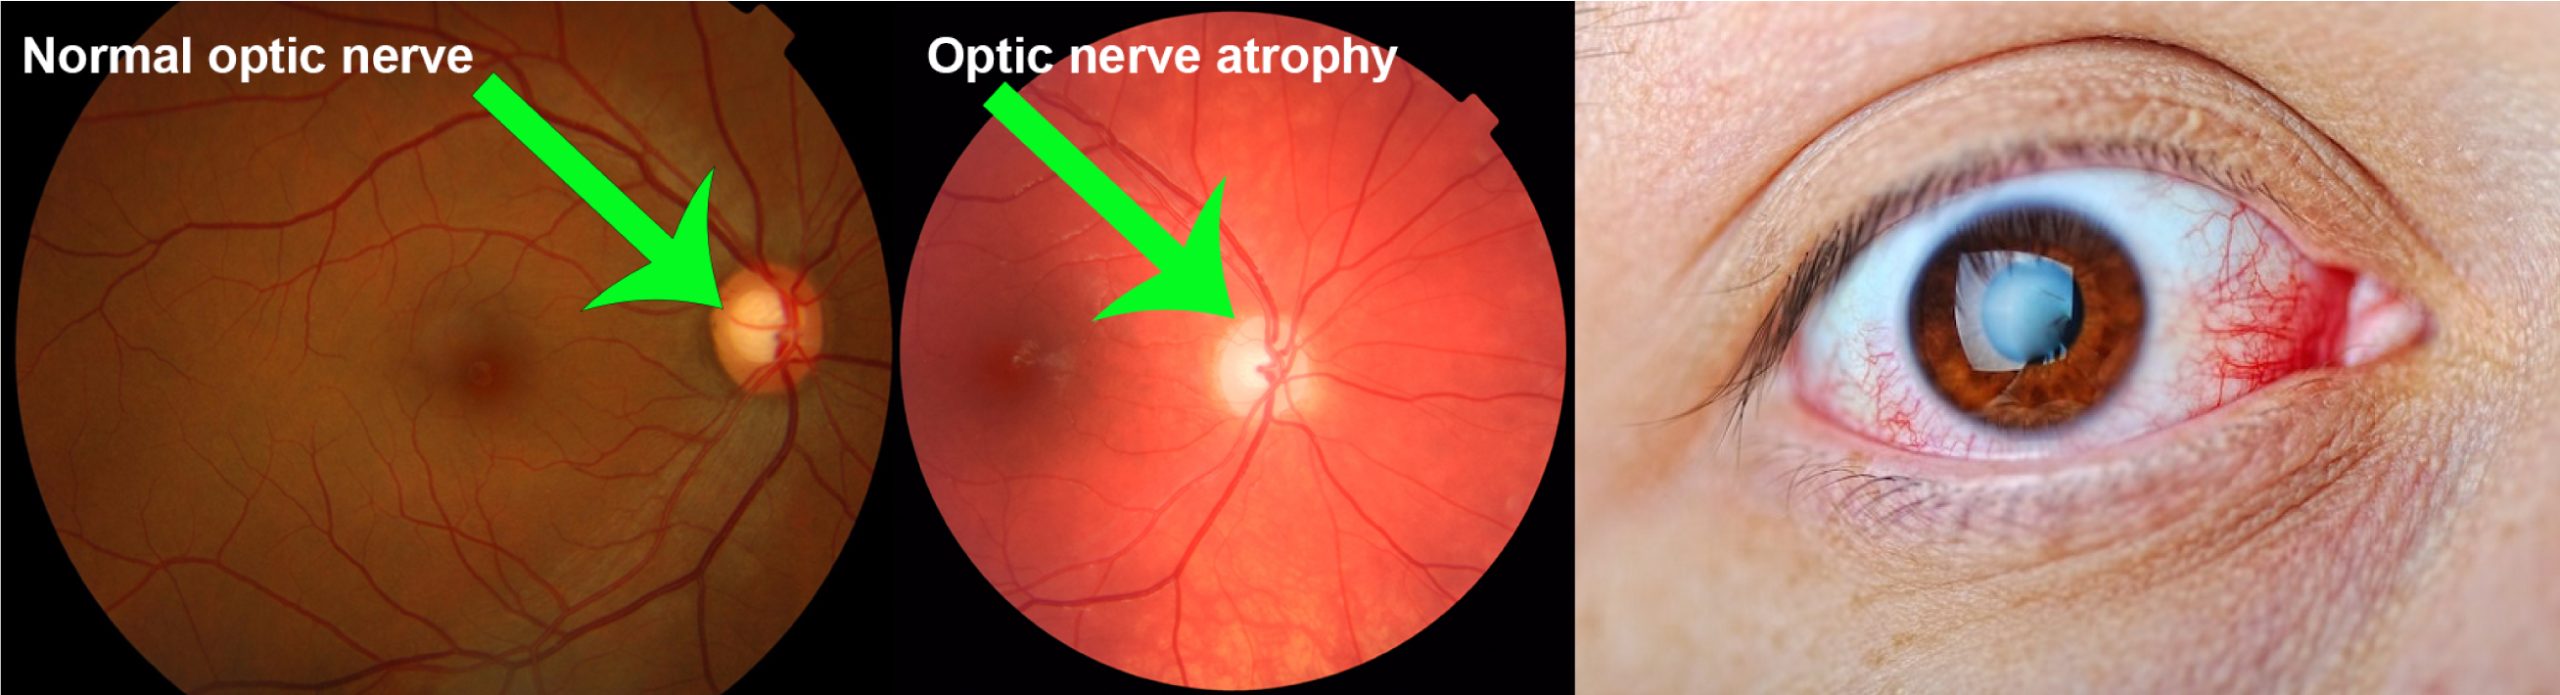

视神经萎缩 (OA)

视神经萎缩 (OA) 是指视神经的退化,视神经是连接视网膜和大脑的关键通路,其退化是由各种疾病引起的视神经纤维、神经节细胞及其轴突的病理损伤所致。这种退化会导致视功能逐渐下降,其特征是不同程度的视觉功能障碍,包括视力下降、视野缺损 (通常是向心性缩小)、色觉改变,严重时甚至失明。临床上,OA 分为原发性 (下行性),即神经本身直接受累,和继发性 (上行性),即损伤由其他疾病引起,如颅内压升高、炎症或血管问题。诊断依赖于评估视力下降、视野缺损、视盘苍白或苍白以及视网膜神经纤维层缺损。在眼底检查中,早期体征包括视盘苍白、边缘清晰的视神经乳头苍白或苍白、视网膜血管变细和黄斑中心凹反射模糊。有效的西医治疗 OA 取决于识别和解决根本原因,因为逆转损伤通常很困难。

在中医理论中,视神经萎缩被称为“青盲”,其主要特征是视盘颜色变淡,视力逐渐下降,严重时可能导致失明。若发生在儿童身上,则被称为“小儿青盲”。此病在中医看来,其病因病机复杂多样:可能是由于情志抑郁,肝气不舒,导致经络郁滞,目窍闭塞,神光无法正常发越;也可能是由于先天禀赋不足,肝肾两亏,精虚血少,无法滋养眼部,导致目窍萎缩,神光消散;或是因久病劳累或失血过多,气血不足,失于濡养,造成目窍萎缩,神光混灭;甚至可能是头眼外伤,导致目系受损,或是脑部肿瘤压迫目系,致使脉络瘀阻,目窍闭塞,神光混灭。值得注意的是,中医中药配合针灸在调理此病通常能取得较好的疗效。